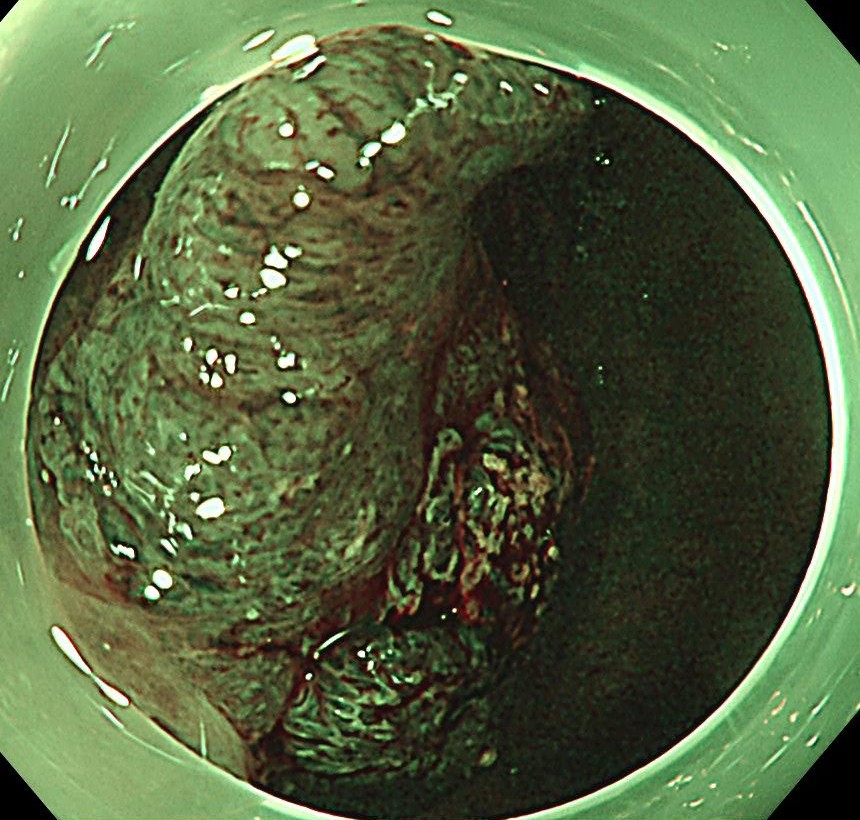

狭帯域光観察(NBI)では明らかにV型パターンであり、悪性を疑いますが、内視鏡治療可能と診断しました。